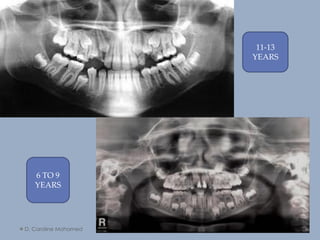

11-13

YEARS

6 TO 9

D. Caroline Mohamed64 11-13 YEARS 6 TO 9 YEARS